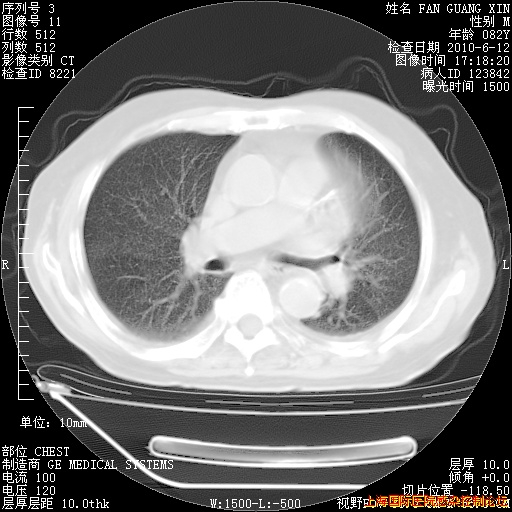

6月12日肺窗

整整相隔30天的肺部CT好像有所好转啊。甲强龙减量第3天,需要观察体温。